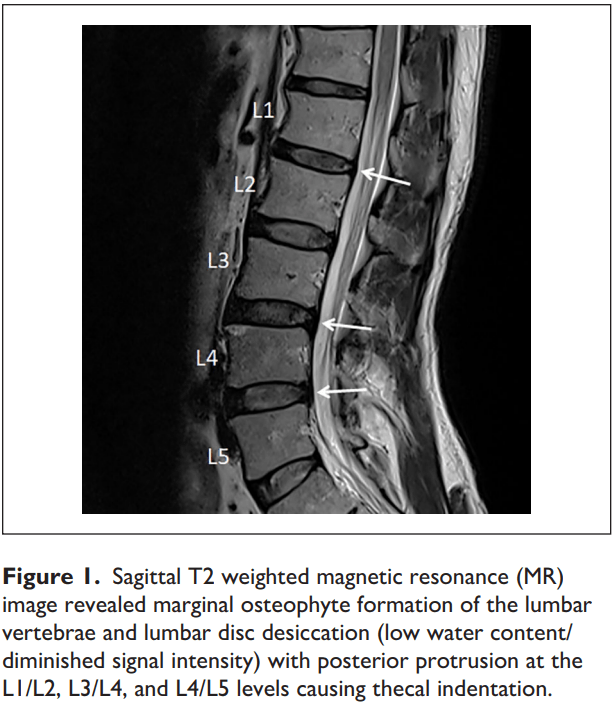

Cureus Herniating Intradural Disc at Lumbar L4L5 Level A Case Report Herniated Disc Pain Testicle Chronic testicular pain is a common presenting problem in urology and general practitioner's clinics [1]. Lumbar disk herniation (ldh), which presents with severe lower back pain (lbp) with radiation to the leg, can affect an individual’s normal functions. 8 possible causes of testicular pain, what to know and when to see a doctor. Testicular pain can have several causes, including. Herniated Disc Pain Testicle.